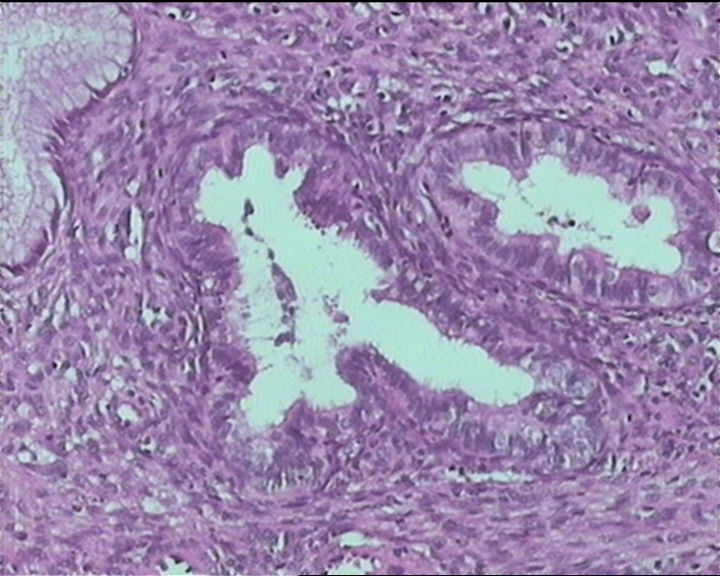

54岁女性,临床“宫颈息肉”送检;巨检:组织一块1。5*1CM,灰红。

输卵管粘膜化生

It is benign. Benign endocervical polyp with tubal metaplasia.

细胞及腺体均有异形,图6、11、16象有纤维间质反应,考虑高级别上皮内瘤变/原位癌,腺癌不能除外。

Sternberg病理学上诊断宫颈原位腺癌的标准是腺体的上皮去粘液分化,呈乳头状或筛网状增生,核分裂易见,这例显然达不到此标准。此例还是归入到腺上皮不典型增生为好。

杨老师说它是良性的,是个颈管内膜息肉伴输卵管上皮化生,良性